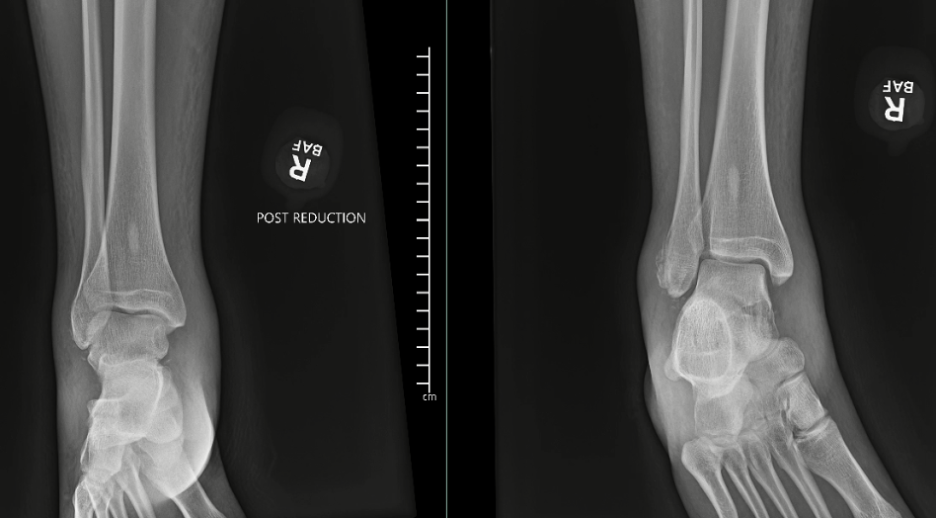

One should obtain plain film radiographs in the emergency department (Figure 1 above) prior to reduction and then following reduction. Multiple postreduction views should confirm proper position of the tibiotalar, subtalar, and talonavicular joints. Following reduction, computerized tomography (CT) scans may assist in identifying any residual intra-articular debris or articular irregularities.6,7 Additionally, one should consider CT results prior to taking the patient to the operative suite. Additionally, 3D-reconstructed CT scans may help scrutinize reduction and aid in surgical planning (Figure 2 below).

Following imaging, the patient underwent a hematoma block of the ankle and subtalar joint with lidocaine. Once properly anesthetized, we bent the knee and successfully reduced the deformity (Figure 4 above). Physicians applied a plaster splint for stability and admitted this patient for surgery the following morning. Surgeons felt the subtalar joint had residual instability. Additionally, the osseous debris in the posterior facet of the subtalar joint was difficult to ignore.